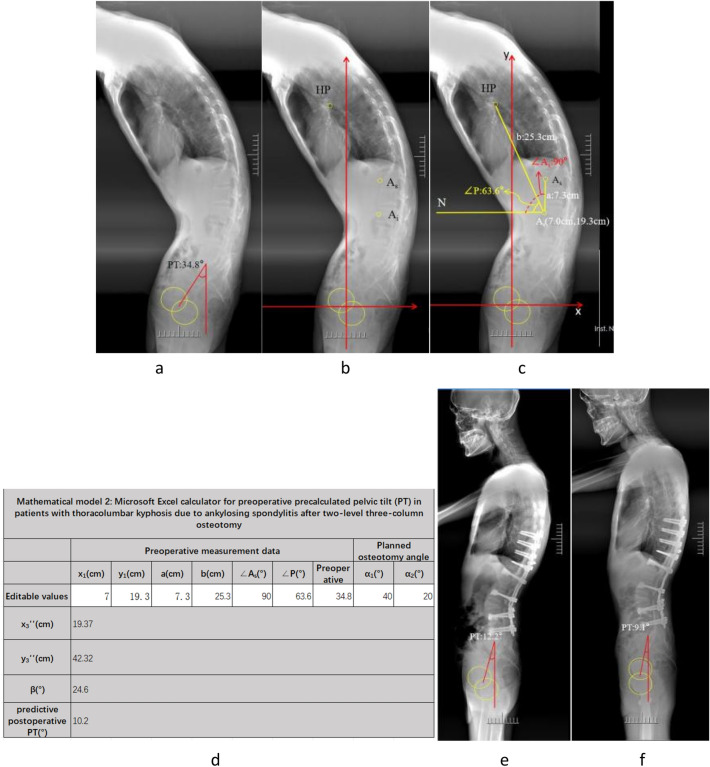

Methods: A total of 20 patients with AS, including 19 men and one woman, who underwent three-column osteotomy from April 2017 to April 2021, in the study hospital were retrospectively reviewed. Spinopelvic parameters, including global kyphosis, pelvic incidence, sacral slope, PT, sagittal vertical axis, horizontal distance between hip axis and hilus pulmonis (HDHH), measured on preoperative, postoperative, and final follow-up radiographs were analyzed. A coordinate diagram was created on the lateral spine radiographs with the hip axis as the origin. The distances and angles between the osteotomy apex, hilus pulmonis, and hip axis were measured, and a mathematical model was established using basic vector functions. The planned osteotomy angle was substituted into the mathematical model to obtain precalculated postoperative PT. Paired sample t-test was performed to determine the differences between planned osteotomy angle and actual osteotomy angle and between predictive postoperative PT and actual postoperative PT.

Results: Seven patients underwent single-level osteotomy, and 13 patients underwent two-level osteotomy. No significant difference was observed between the planned osteotomy angle and the actual osteotomy angle. No statistically significant difference was found between the precalculated postoperative PT and the actual postoperative PT.

Conclusions: The novel mathematical model was reliable in predicting postoperative PT in patients with AS undergoing three-column osteotomy.